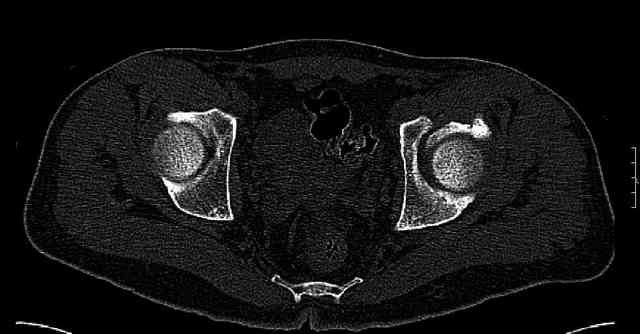

The last two images from the 3-D CT scan certainly makes the fracture look worse than the plan radiographs.

The joint is non-concentric as the head appears to be either "following the caudal segment", or the dome component is displaced from the tethered head... or so it seems... and he's young... so, many fracture surgeons would recommend reduction and fixation.

Some more images. Does it help to guess which part of the acetabulum is displaced?

Normal appearing SI joints and a healed posterior column limb... my bet's on caudal segment displacement.